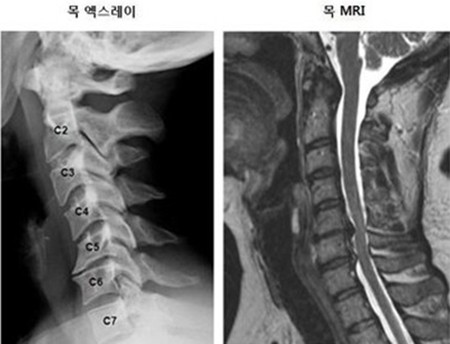

목 디스크는 목의 디스크(경추 디스크)에서 출현하는 질환으로, 경추 디스크 사이의 연골판이 터져 디스크 내부 물질이 경추 신경을 자극해 통증이나 저림증 등의 증상을 유발 해요. 목 디스크는 일상생활에서의 안 좋은 자세나 많은 운동, 부상 등이 이유가 되는 것이 될 수 있기도하고, 시간이 지날수록 발생 확률이 높아져요. 목 디스크의 증상으로는 목 부위의 통증, 팔의 저림, 근육 약화 등이 있으며, 증상이 난폭한 경우 수술 등의 치료가 필요할 수 있어요. 그리하나 대개의 경우 치료 없이도 시간이 지나면 증상이 호전되는 경우가 대부분입니다.

척수라는 중추 신경은 목뼈를 통과해 목 아래 감각과 운동 신경에 영향을 끼치기 때문에 목 디스크 증상들이 나타나면 신속하고 빠른 대처가 필요해요. 목디스크 치료형식으로 주로 초기 스탭에는 물리치료나 약물을 통해 대개의 환자들이 호전돼요. 그렇지 않다고 하면 신경 성형술과 차단술이라고 부르는 뼈주사 목디스크 치료방법을 이용하는데, 이 치료방법은 통증이 있는 신경 부위에 약물을 삽입하는 것입니다.

수술 방법에도 많은가 있다고 하는데 개괄적으로 설명을 하면 목을 절개해 망가진 디스크를 제거한 뒤 뼈를 하나로 유합하는 방법, 인공 디스크 투입술, 내시경을 활용해 바깥으로 빠져나온 수핵을 없애는 수술법 등이 있다고 합니다.